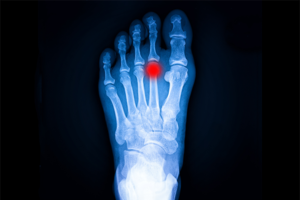

El diagnóstico se realiza mediante exploración clínica especializada y pruebas de imagen, como radiografías o resonancia magnética. En Podoactiva, contamos con tecnología avanzada para una valoración biomecánica detallada que ayude a detectar y evaluar la progresión de la enfermedad de Freiberg.

Se solicita radiografía dorsoplantar de los pies y se deriva a estudio biomecánico. Tras los resultados de la radiografia se observa una pérdida de la curvatura normal de la 2º cabeza metatarsal, compatible con la enfermedad de Freiberg.

Es un tipo de metatarsalgia que consiste en una necrosis avascular que produce un aplanamiento de la cabeza metatarsal debido en gran parte a un traumatismo repetitivo en dicho hueso. Su evolución en el tiempo produce una deformidad permanente de la articulación que genera dolor en la zona al caminar (metatarsalgia).

En la plataforma de presiones se aprecia un aumento significativo de las cargas en el antepie derecho, coincidiendo el punto de máxima carga en la zona de apoyo del 2º metatarsiano. Aunque la sobrecarga no siempre es el motivo de esta patología, si que produce un aumento de los síntomas.